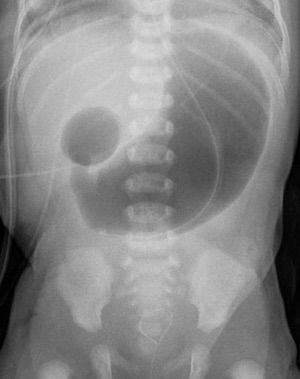

Double Bubble Sign

Duodenal Atresia